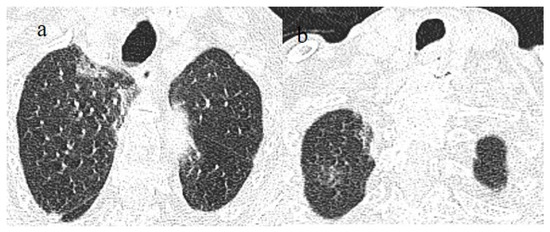

3.3.1. Acute Respiratory Distress Syndrome

3.3.2. Pneumomediastinum and Pneumothorax

3.3.3. Pulmonary Fibrosis